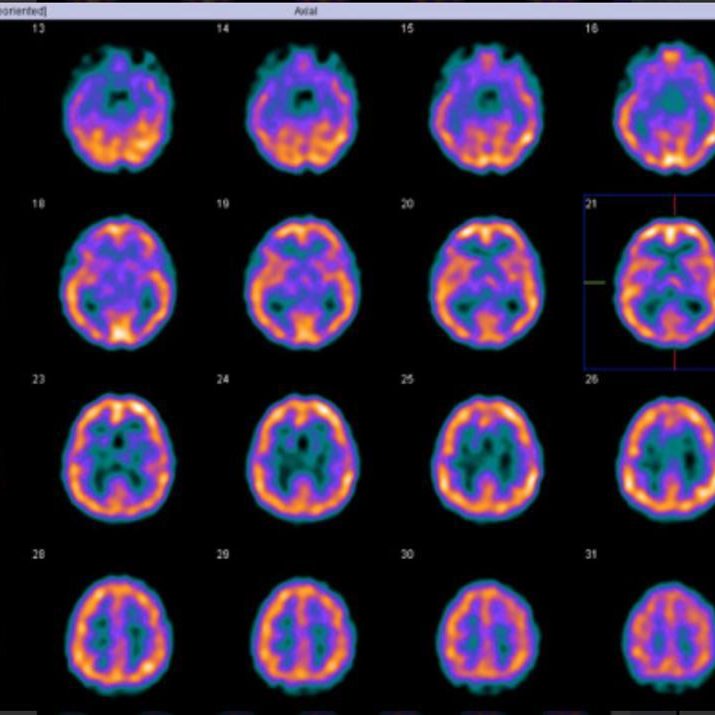

¿Cómo se realiza una gammagrafía ósea?

Una gammagrafía ósea implica inyectar una cantidad muy pequeña de material radiactivo (marcador) dentro de una vena. La sustancia viaja a través de la sangre hasta los huesos y órganos. A medida que esta va desapareciendo, emite un poco de radiación. Esta es detectada por una cámara que lentamente escanea el cuerpo.

Toma imágenes del marcador que hay en sus huesos. El técnico puede solicitarle que cambie de posición durante el procedimiento. Esto ayuda a obtener imágenes desde diferentes ángulos. Una gammagrafía ósea de todo el cuerpo tarda aproximadamente 1 hora en completarse.

¿Que detecta la cámara gamma?

La cámara gamma detecta las emisiones de energía de la radiosonda en su cuerpo y las convierte en una imágen. La cámara gamma de por sí no emite ninguna radiación. Tiene detectores de radiación denominados cabezas de cámara gamma.